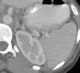

Intrasplenic hematoma